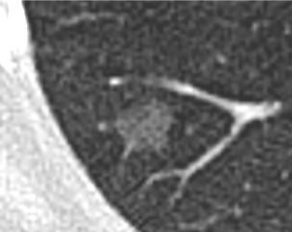

肺腺鳞癌 PULMONARY ADENOCARCINOMA LEPIDIC PATTERN |

出血 |

False Negative and False Positive

阴性 |

假阴性

再活检:肺腺鳞癌 |

活检:阴性 |

肺泡出血 |